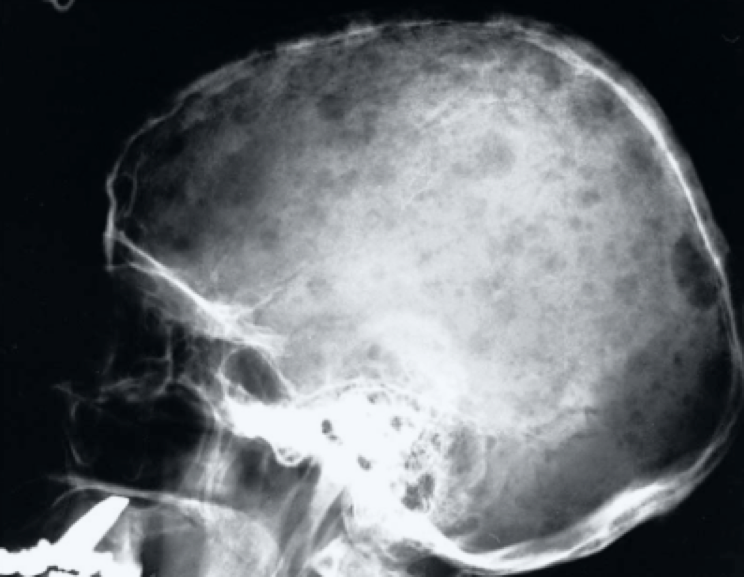

Question 1

Question

In what disease will you see this in?

Answer

• Multiple Myeloma

• Paget's Disease

Question 2

• Breast Cancer

• Meningitis